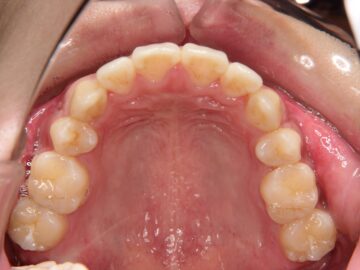

ご相談時

小学生の頃は上下の前歯が当たっていたのに、今は上下の前歯が咬みあわない。

開咬(咬み合わせ合わせが開いている状態)は、一番治しにくい不正咬合です。まず、不安定な顎の位置を改善するためにスプリント療法を行った方がいいと考えました。開咬量も大きいので、当院で行っているアンカースクリューではなく、プレートタイプのアンカーを口腔外科でつけてもらって治療することを勧めました。口腔周囲筋機能訓練も重要です。